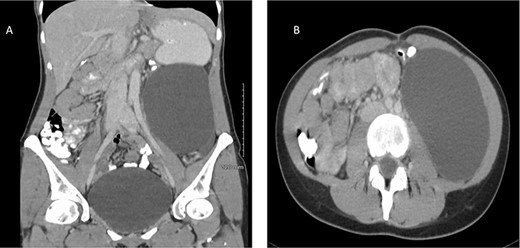

Subsequent computed tomography (CT) scan revealed a lesion in the retroperitoneum, measuring 11 cm in coronal plane and resulting in the anterior displacement of the descending colon (Fig. 1).

Contrast-enhanced CT of a 32-year-old woman presenting with chronic abdominal pain and a mass in left iliac fossa. The image demonstrates a retroperitoneal space occupying lesion measuring 11 cm in coronal plane (A) and resulting in anterior displacement of the descending colon (B).